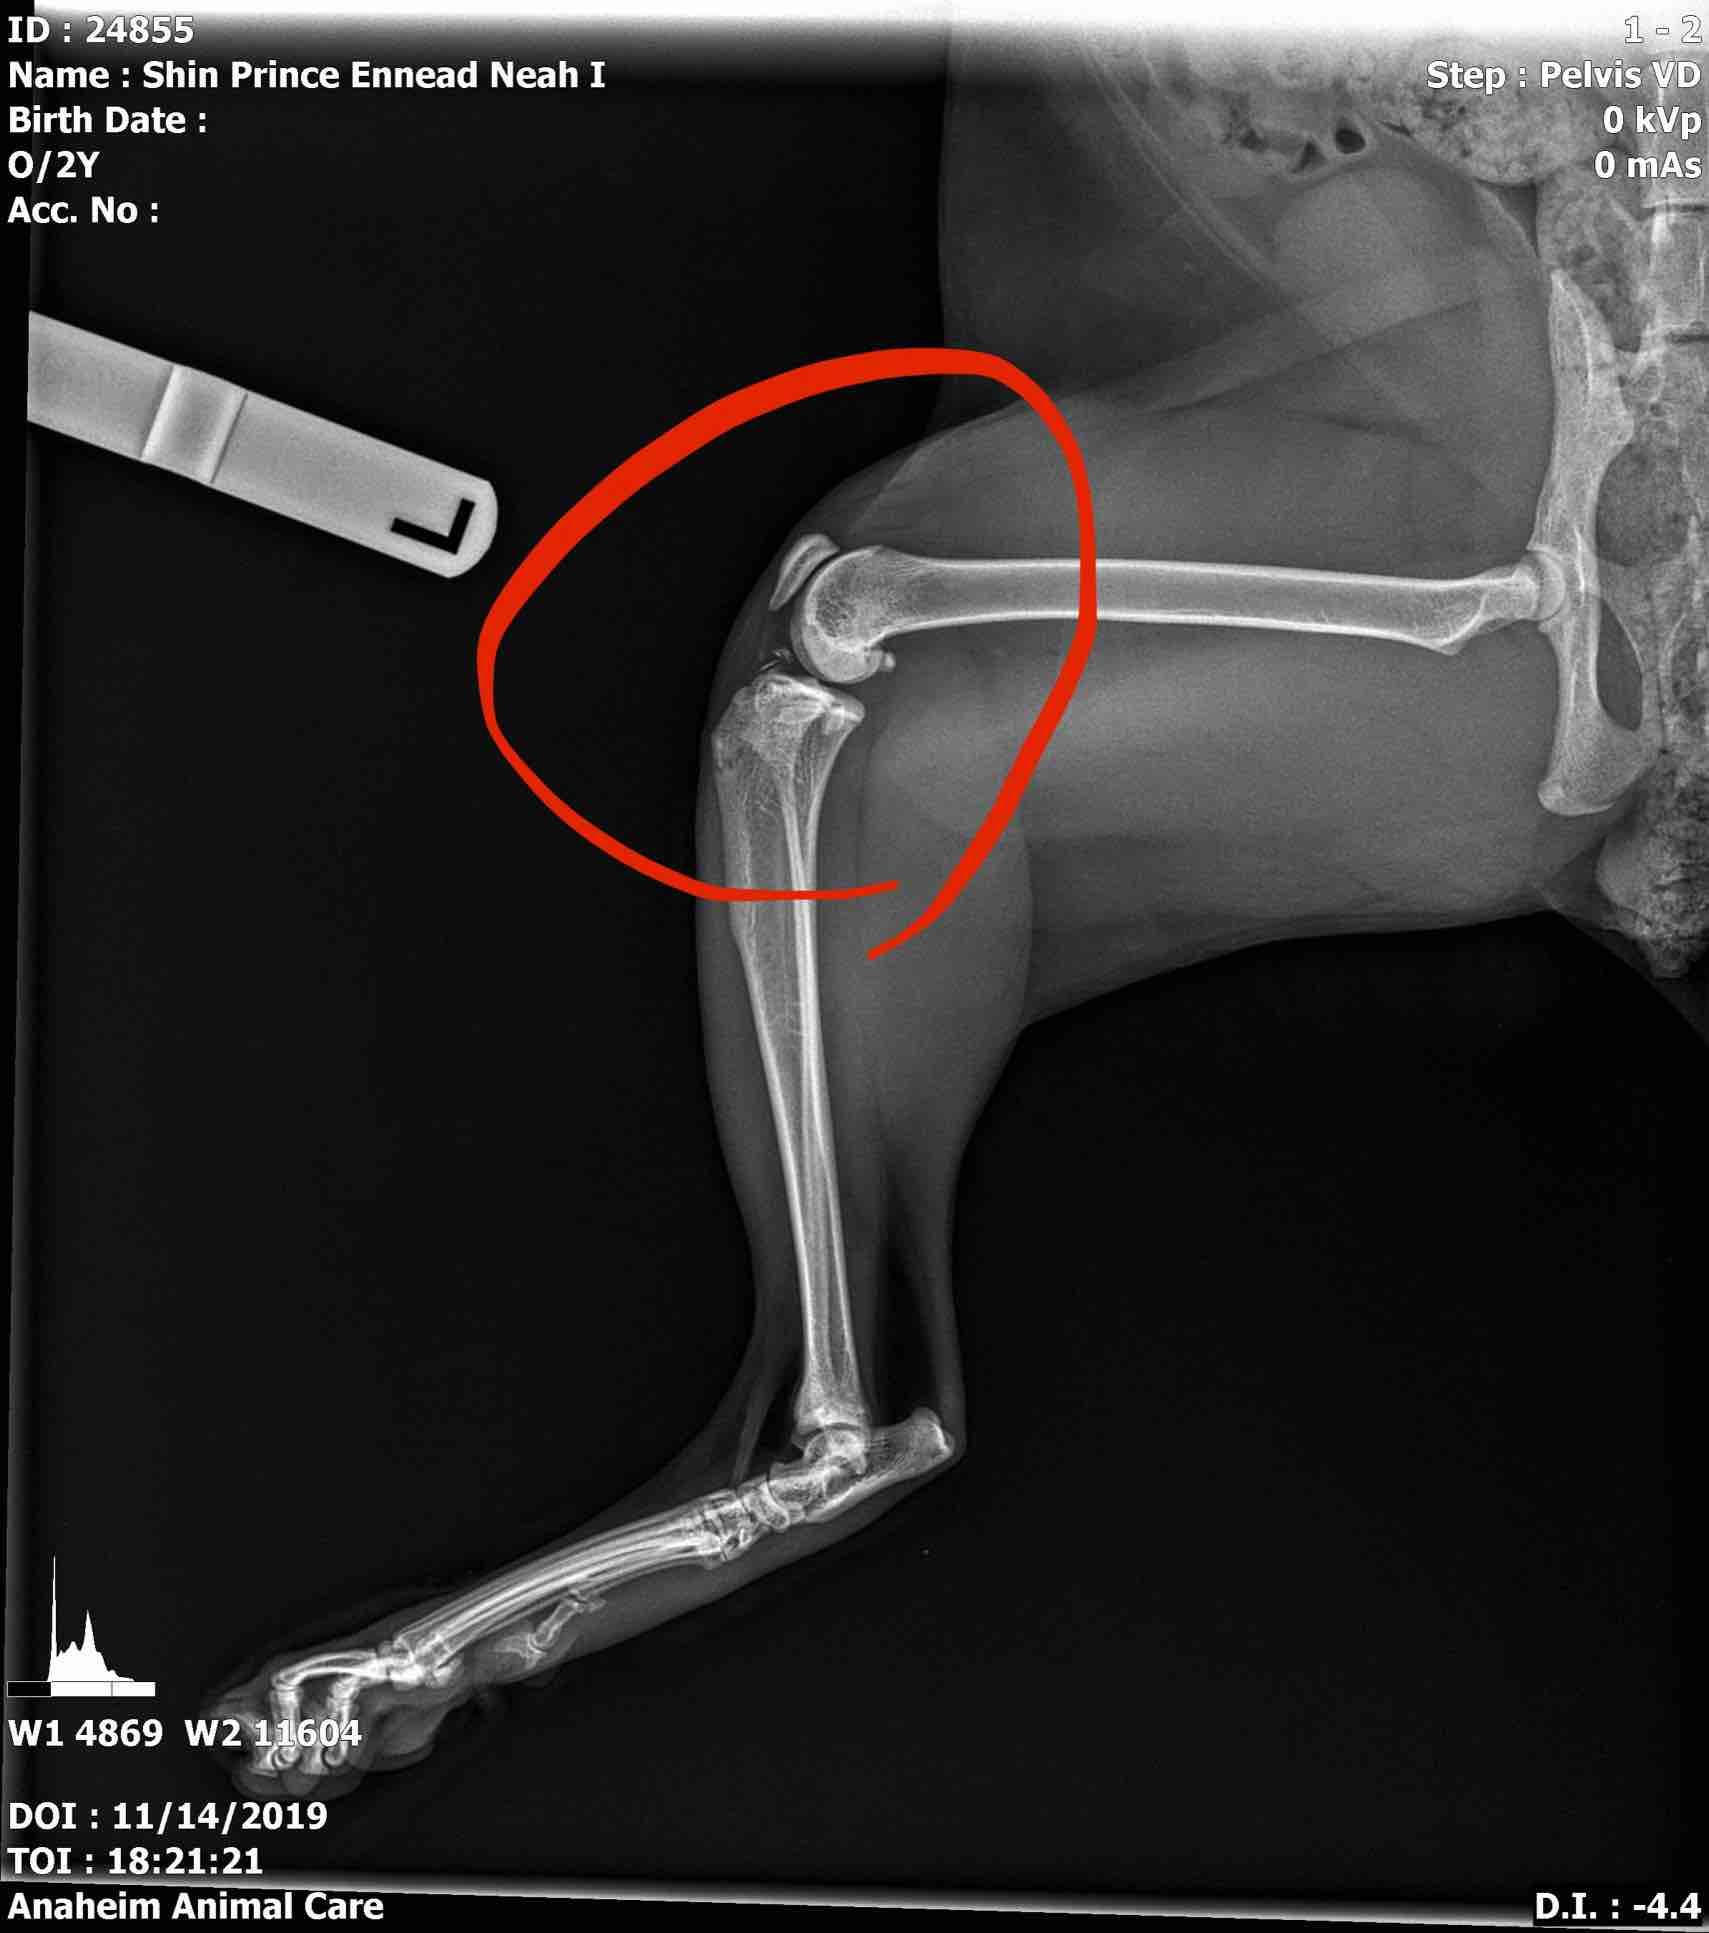

Pet's info: Cat | Savannah Cat | Male | neutered | 2 years and 5 months old | 18 lbs

Other doctor commented nothing seemed wrong. But if those tiny pieces are bone splinter, he would have to do surgery, right...? How much does if usually range? He is eating/drinking good, walking/jumping/running -though I asked him not to. But after taking meds given by doctor, he seems having constipation. Unsure but foul odor is coming out from his bottom hole.

I'm not really seeing bone splinters on the knee/circled area. If you mean the free moving bone, that is the knee-cap and is a normal finding. There could be a tiny bit of debris in the joint capsule surrounding, but it is hard to tell. It would be best to have Neah evaluated by an orthopedic surgeon to determine if surgery is needed. They can also provide you with cost estimates depending on what care is needed as prices will vary by individual clinic. Some medications can cause changes to bowel habits. If Naeh seems in a lot of distress or very uncomfortable, I would let your vet know in case they need to add in a laxative or change medications to help.